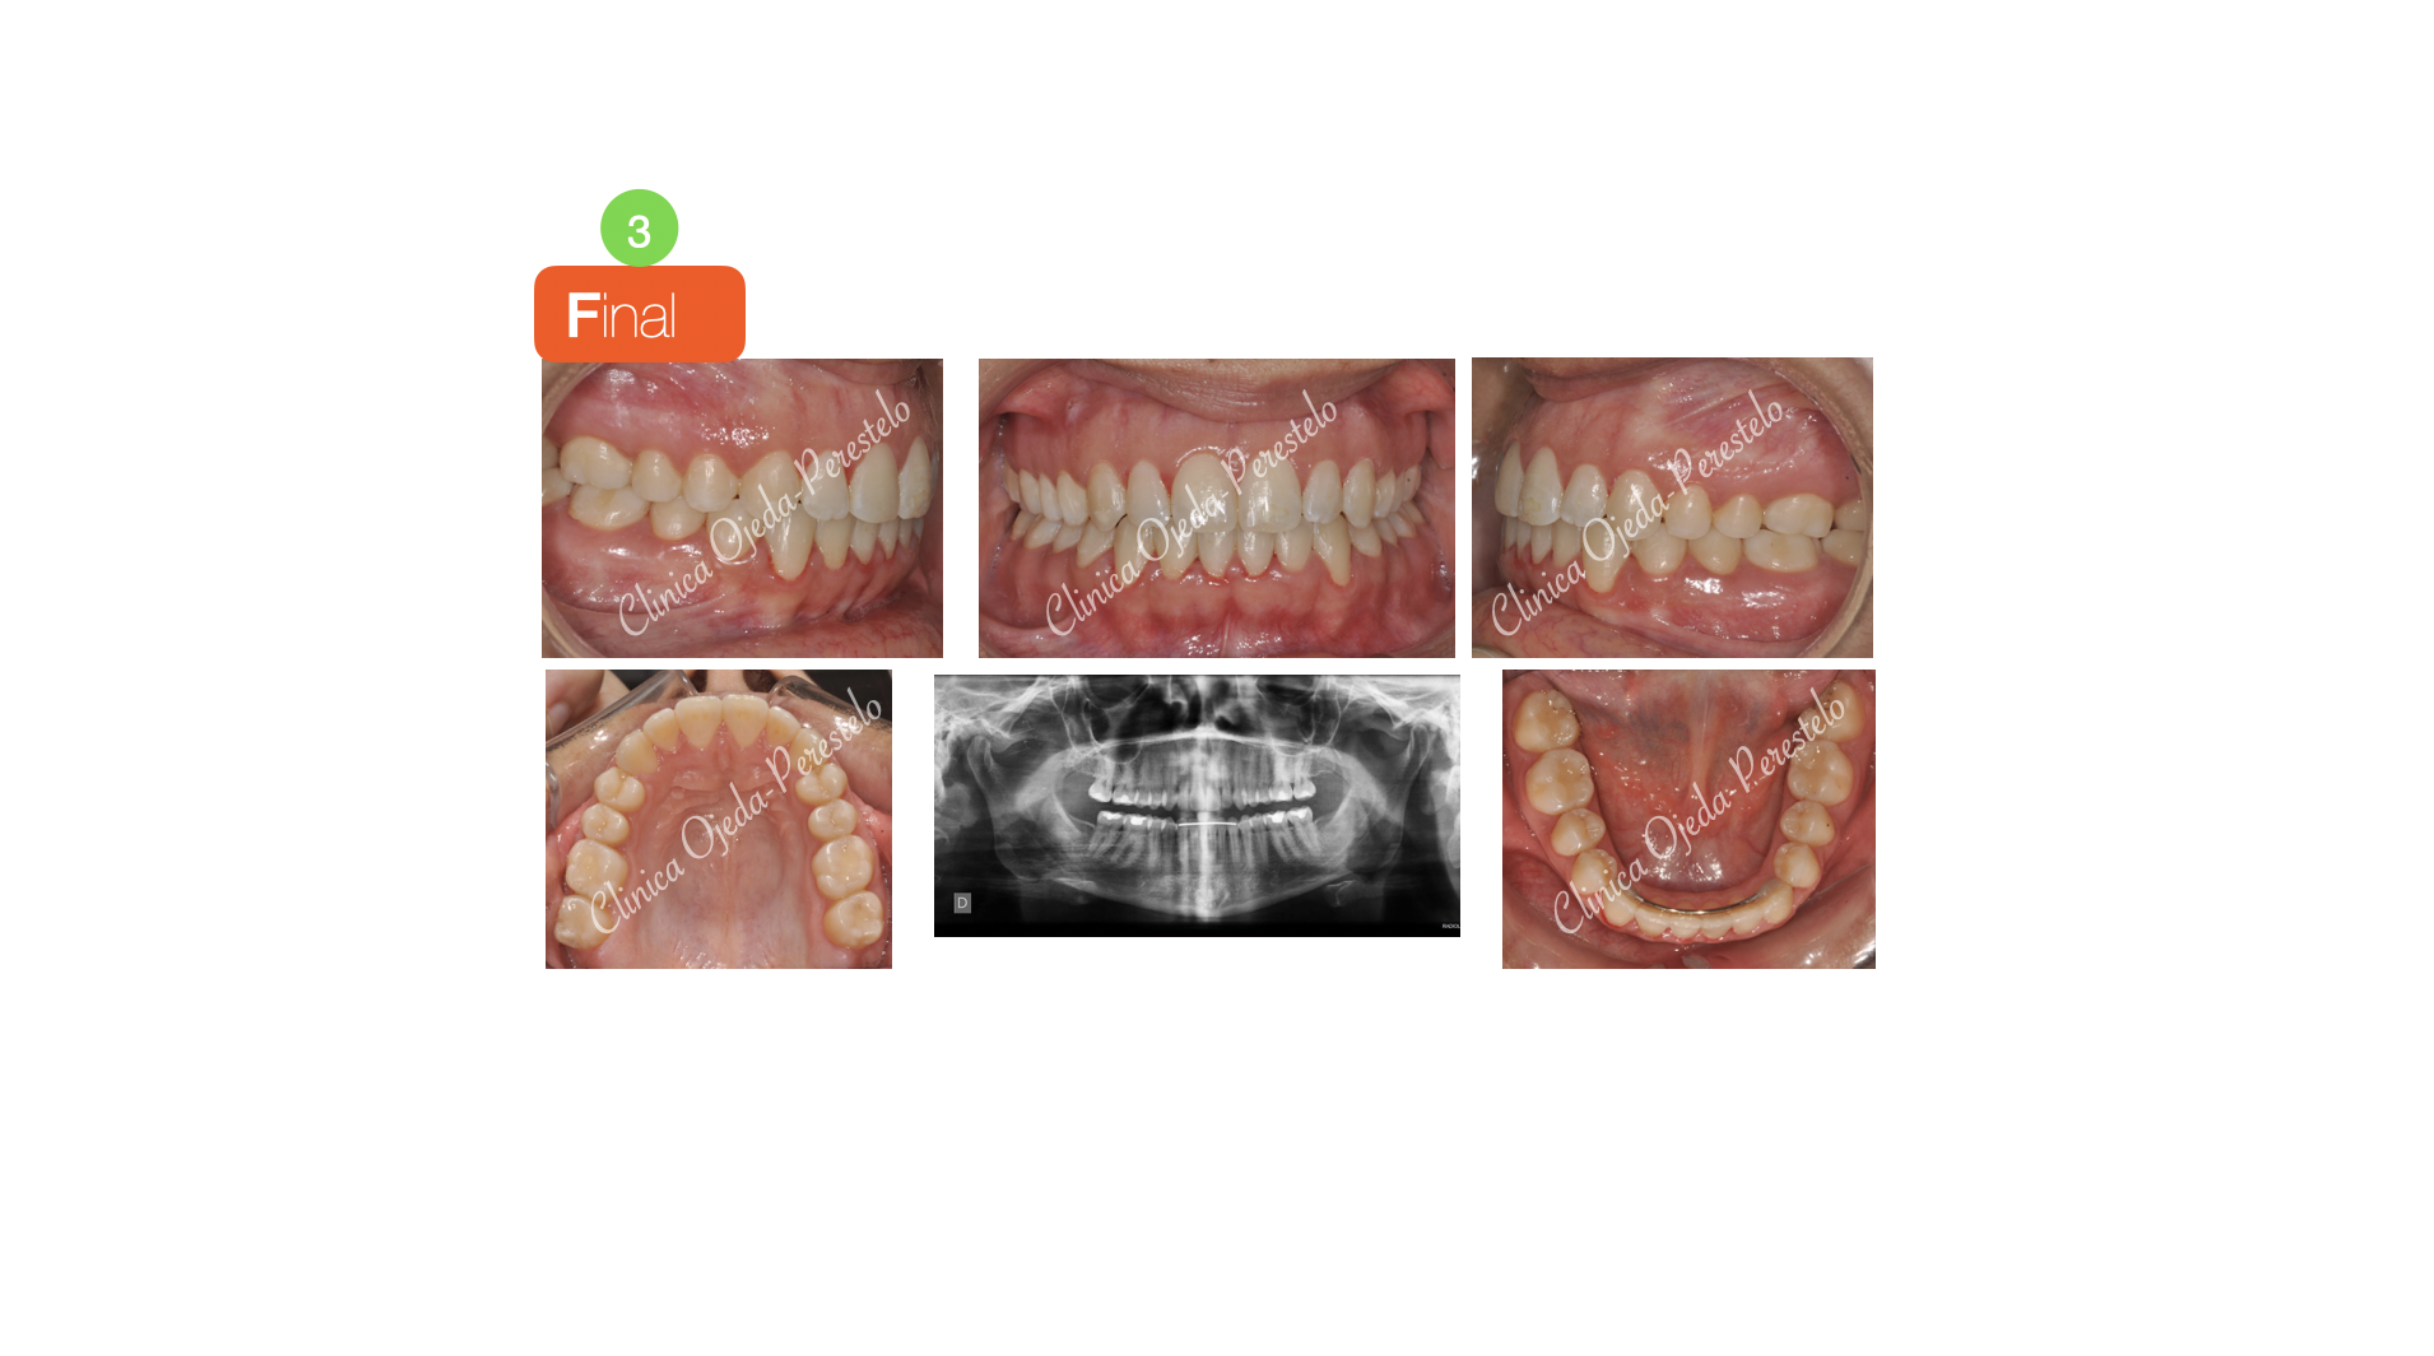

Durante el tratamiento  hemos realizado expansión con intrusión molar y extrusión incisiva combinando los  alineadores con elásticos intermaxilares. En la arcada mandibular hemos tenido que realizar un ligero stripping a efectos de dotarle de un correcto alineamiento a las piezas dentarias.

Finalmente destacar la mejora de la sonrisa, el centrado de las lineas medias, la correcta articulación dentaria y la optima paralelización radicular alcanzada, entre otros.

El objetivo se ha alcanzado con 63 alineadores superiores y 60 alineadores inferiores con cambio semanal en 16 Meses y 2 semanas.